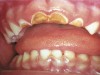

The 2-Year-Old Child with Extensive Caries

Figure 4  Classic early childhood caries demonstrating massive destruction of maxillary anterior teeth.

Figure 4